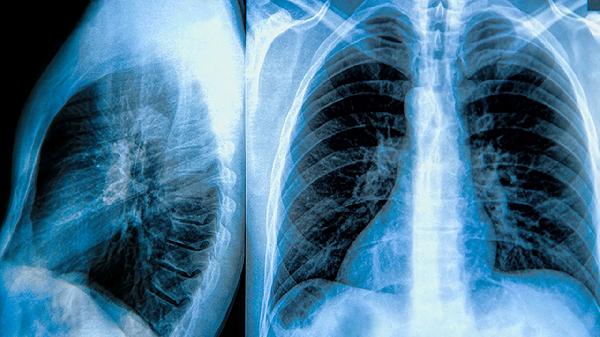

肺大泡患者需注意避免剧烈运动、预防呼吸道感染、戒烟、定期复查肺功能、保持健康体重。肺大泡是肺泡异常扩张形成的囊泡样病变,可能影响呼吸功能。